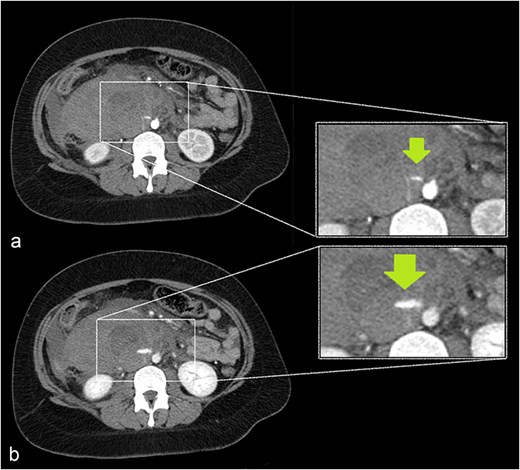

She underwent abdominal sonography followed by contrast-enhanced computed tomography (CECT). Both demonstrated a right-sided retroperitoneal hematoma adjacent to the inferior vena cava and right kidney. A 5 cm ring-shaped structure resembling an empty gestational sac was detected inside the hematoma (Fig. 1). CT showed contrast extravasation representing active bleeding (Figs 2 and 3). Interdisciplinary team discussion, including obstetrician-gynecologists, abdominal surgeons, anesthesiologists, and radiologists, led to the decision for emergency relaparotomy.

A growing slit-like focus of active extravasation was detected on arterial (a) and venous (b) phase scans, obtained 30 and 70 seconds after contrast injection, respectively.